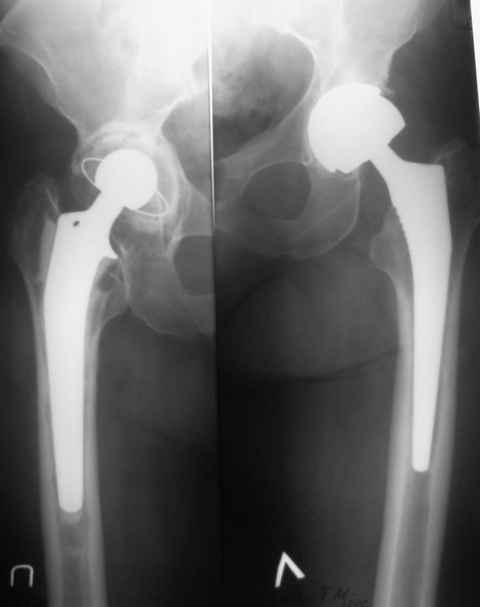

Уважаемые коллеги!Помогите определиться с тактикой лечения осложнения

после эндопротезирования т\бедренного сустава ASR

Пациентка 64 лет, оперирована 2,5 года назад. Выполнено

эндопротезирование левого т\бедренного сустава ASR-XL. Заживление

первично. 10 лет назад выполнялось цементное эндопротезирование

правого т\бедренного сустава. Ч\з год после последней операции

появились боли в области левого сустава, имели преходящий характер,

уменьшались на фоне НПВП. В дальнейшем начались аллергические проблемы

по типу стойкой крапивницы. 6 месяцев назад купированы после

плазмафереза, в настоящее время не купируются. Лечение в НИИ

дерматологии без эффекта. Посев пунктата (примерно 50 мл мутной

серозной жидкости) без роста флоры. В анализах - Le 3,8, С-реактивный

белок -24, СОЭ 25. П\операционный рубец без особенностей, температура

в норме. Боли в области сустава умеренные, но сохраняются, больше

беспокоят кожные проявления (зуд, сыпь). Планируем ревизию.

Вопросы:1)Расценивать как металлоз или скрытую инфекцию? СРБ в 4 раза выше

2)Через спейсер или одномоментно?

3)Если металлоз - оставить ли ножку?

Конечно, удалить все, спейсер, второй этап более предсказуемо, но на

второй ноге цементному протезу более 10 лет, не создаст ли увеличенная

нагрузка проблем для правого сустава?